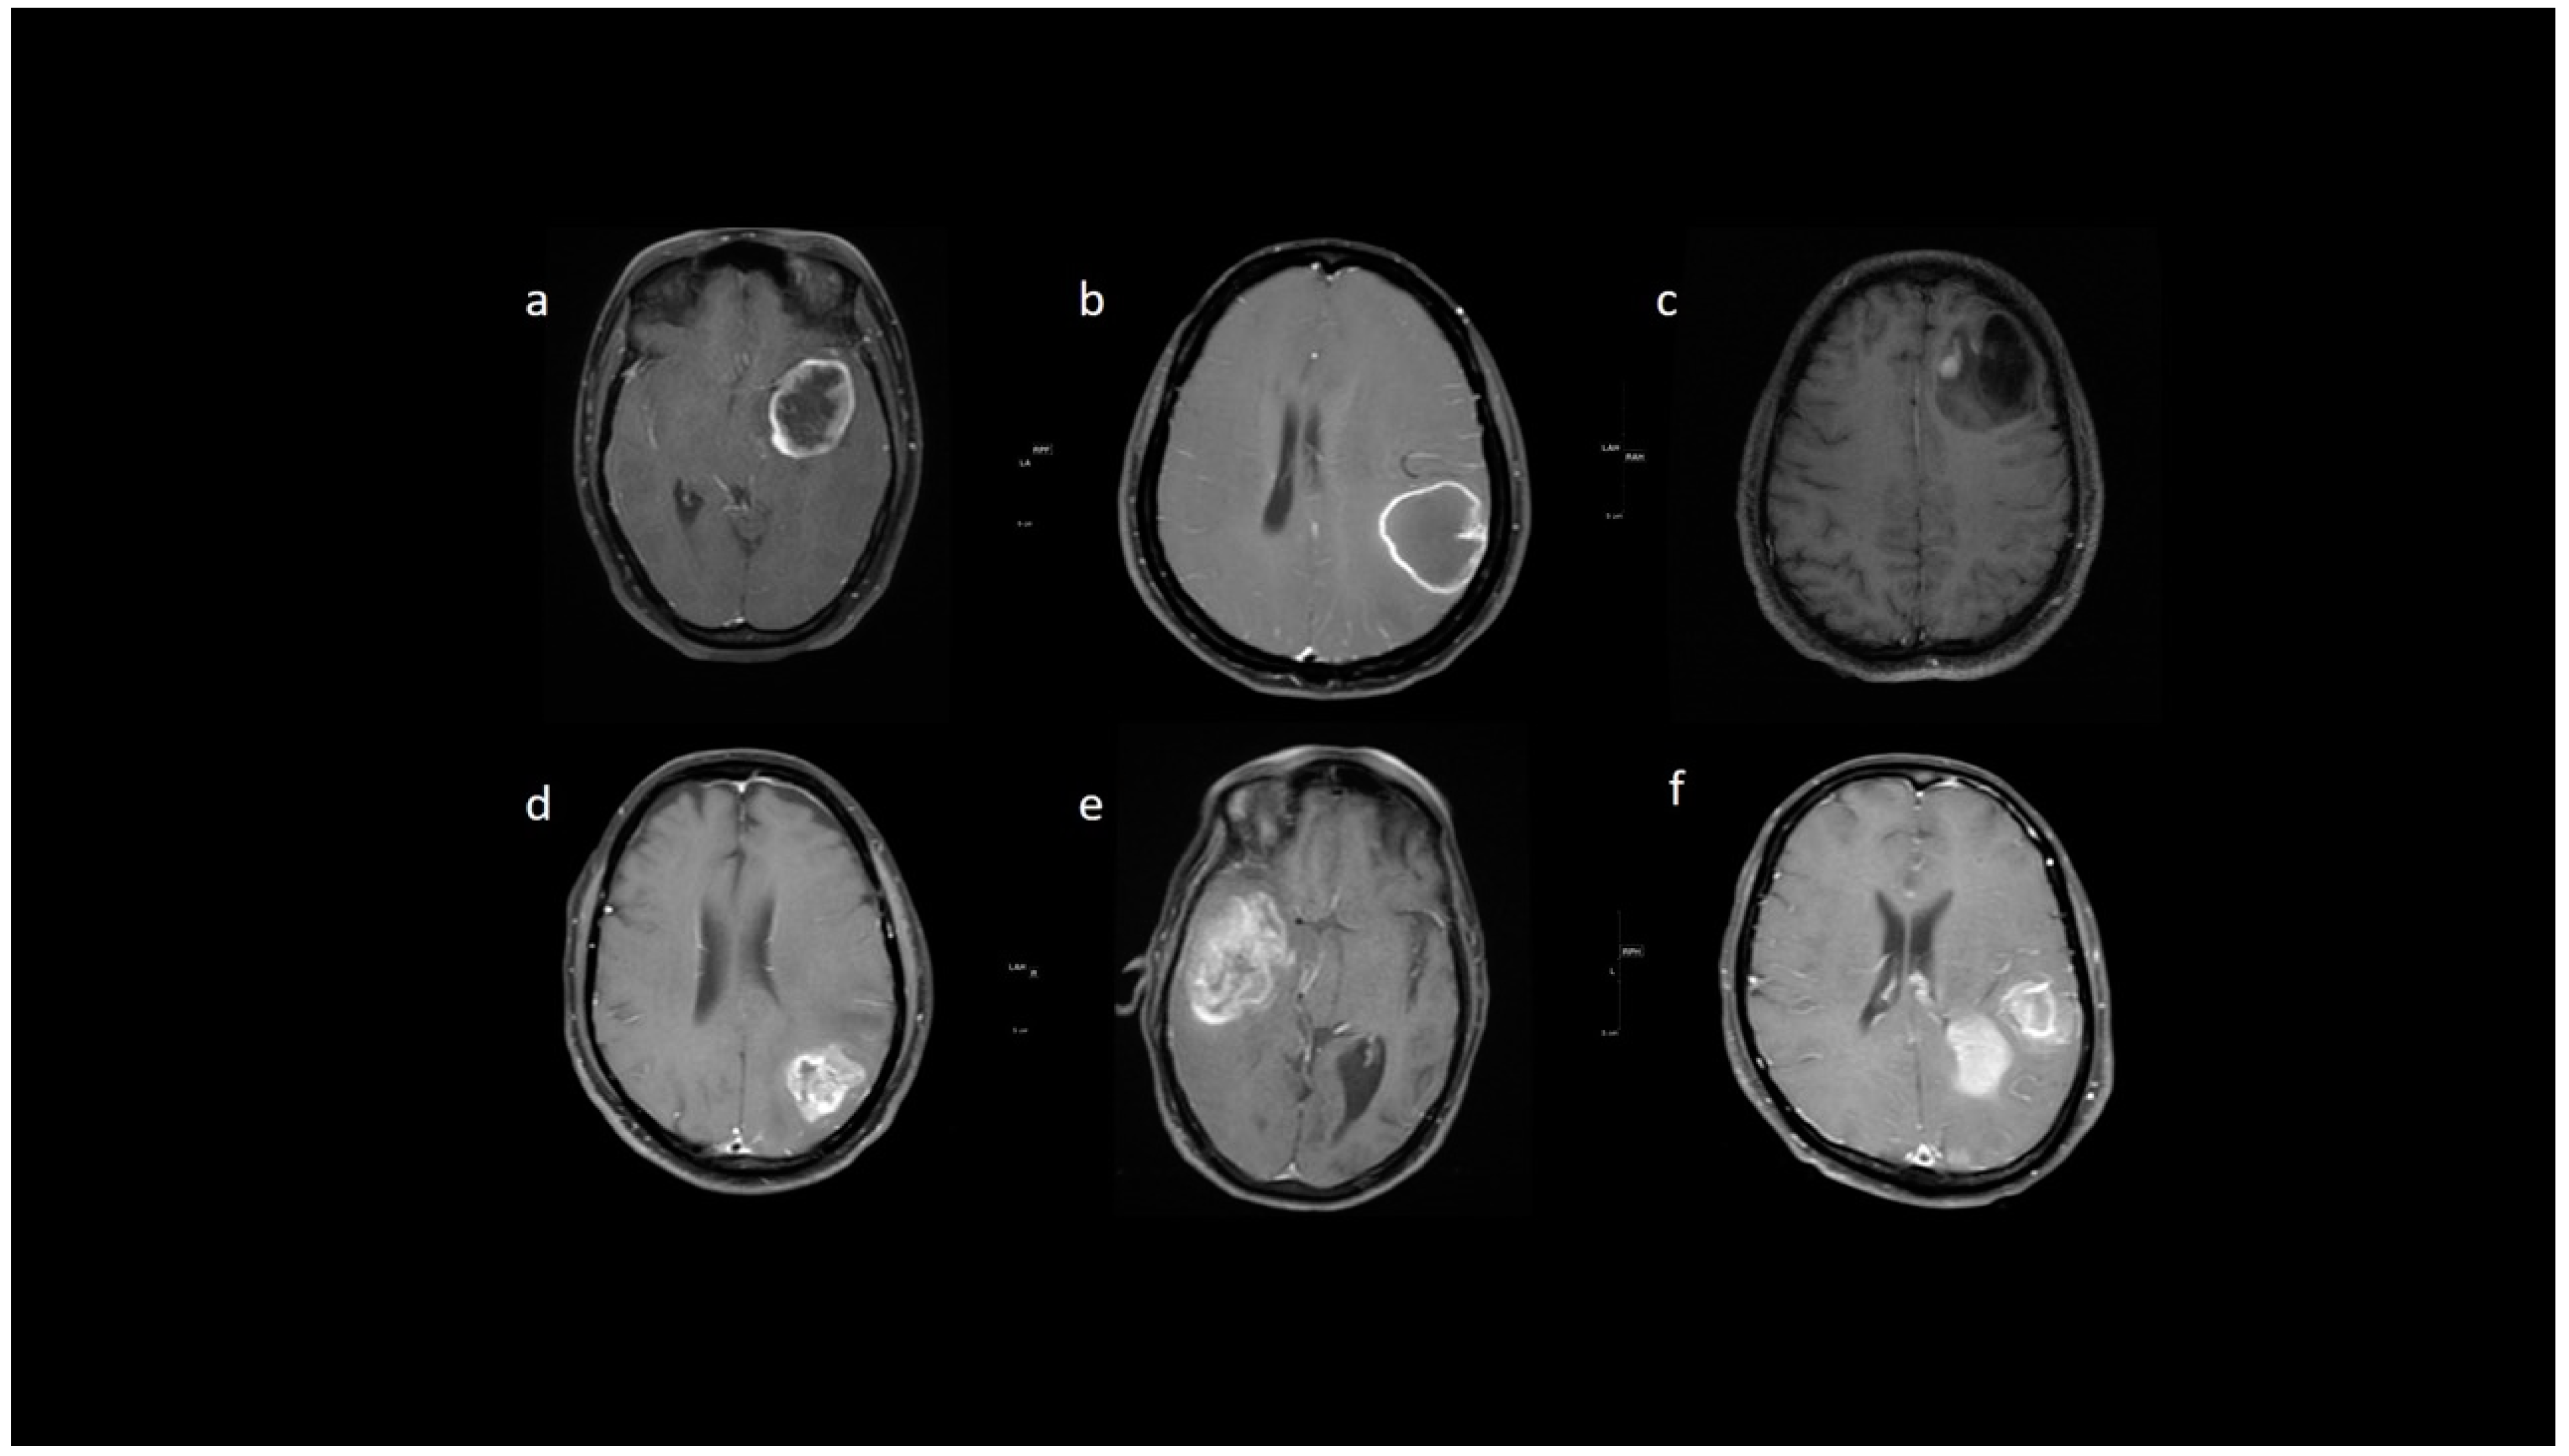

3.2. MRI Parameters of IDH-Wildtype vs. Mutant Phenotype Tumors